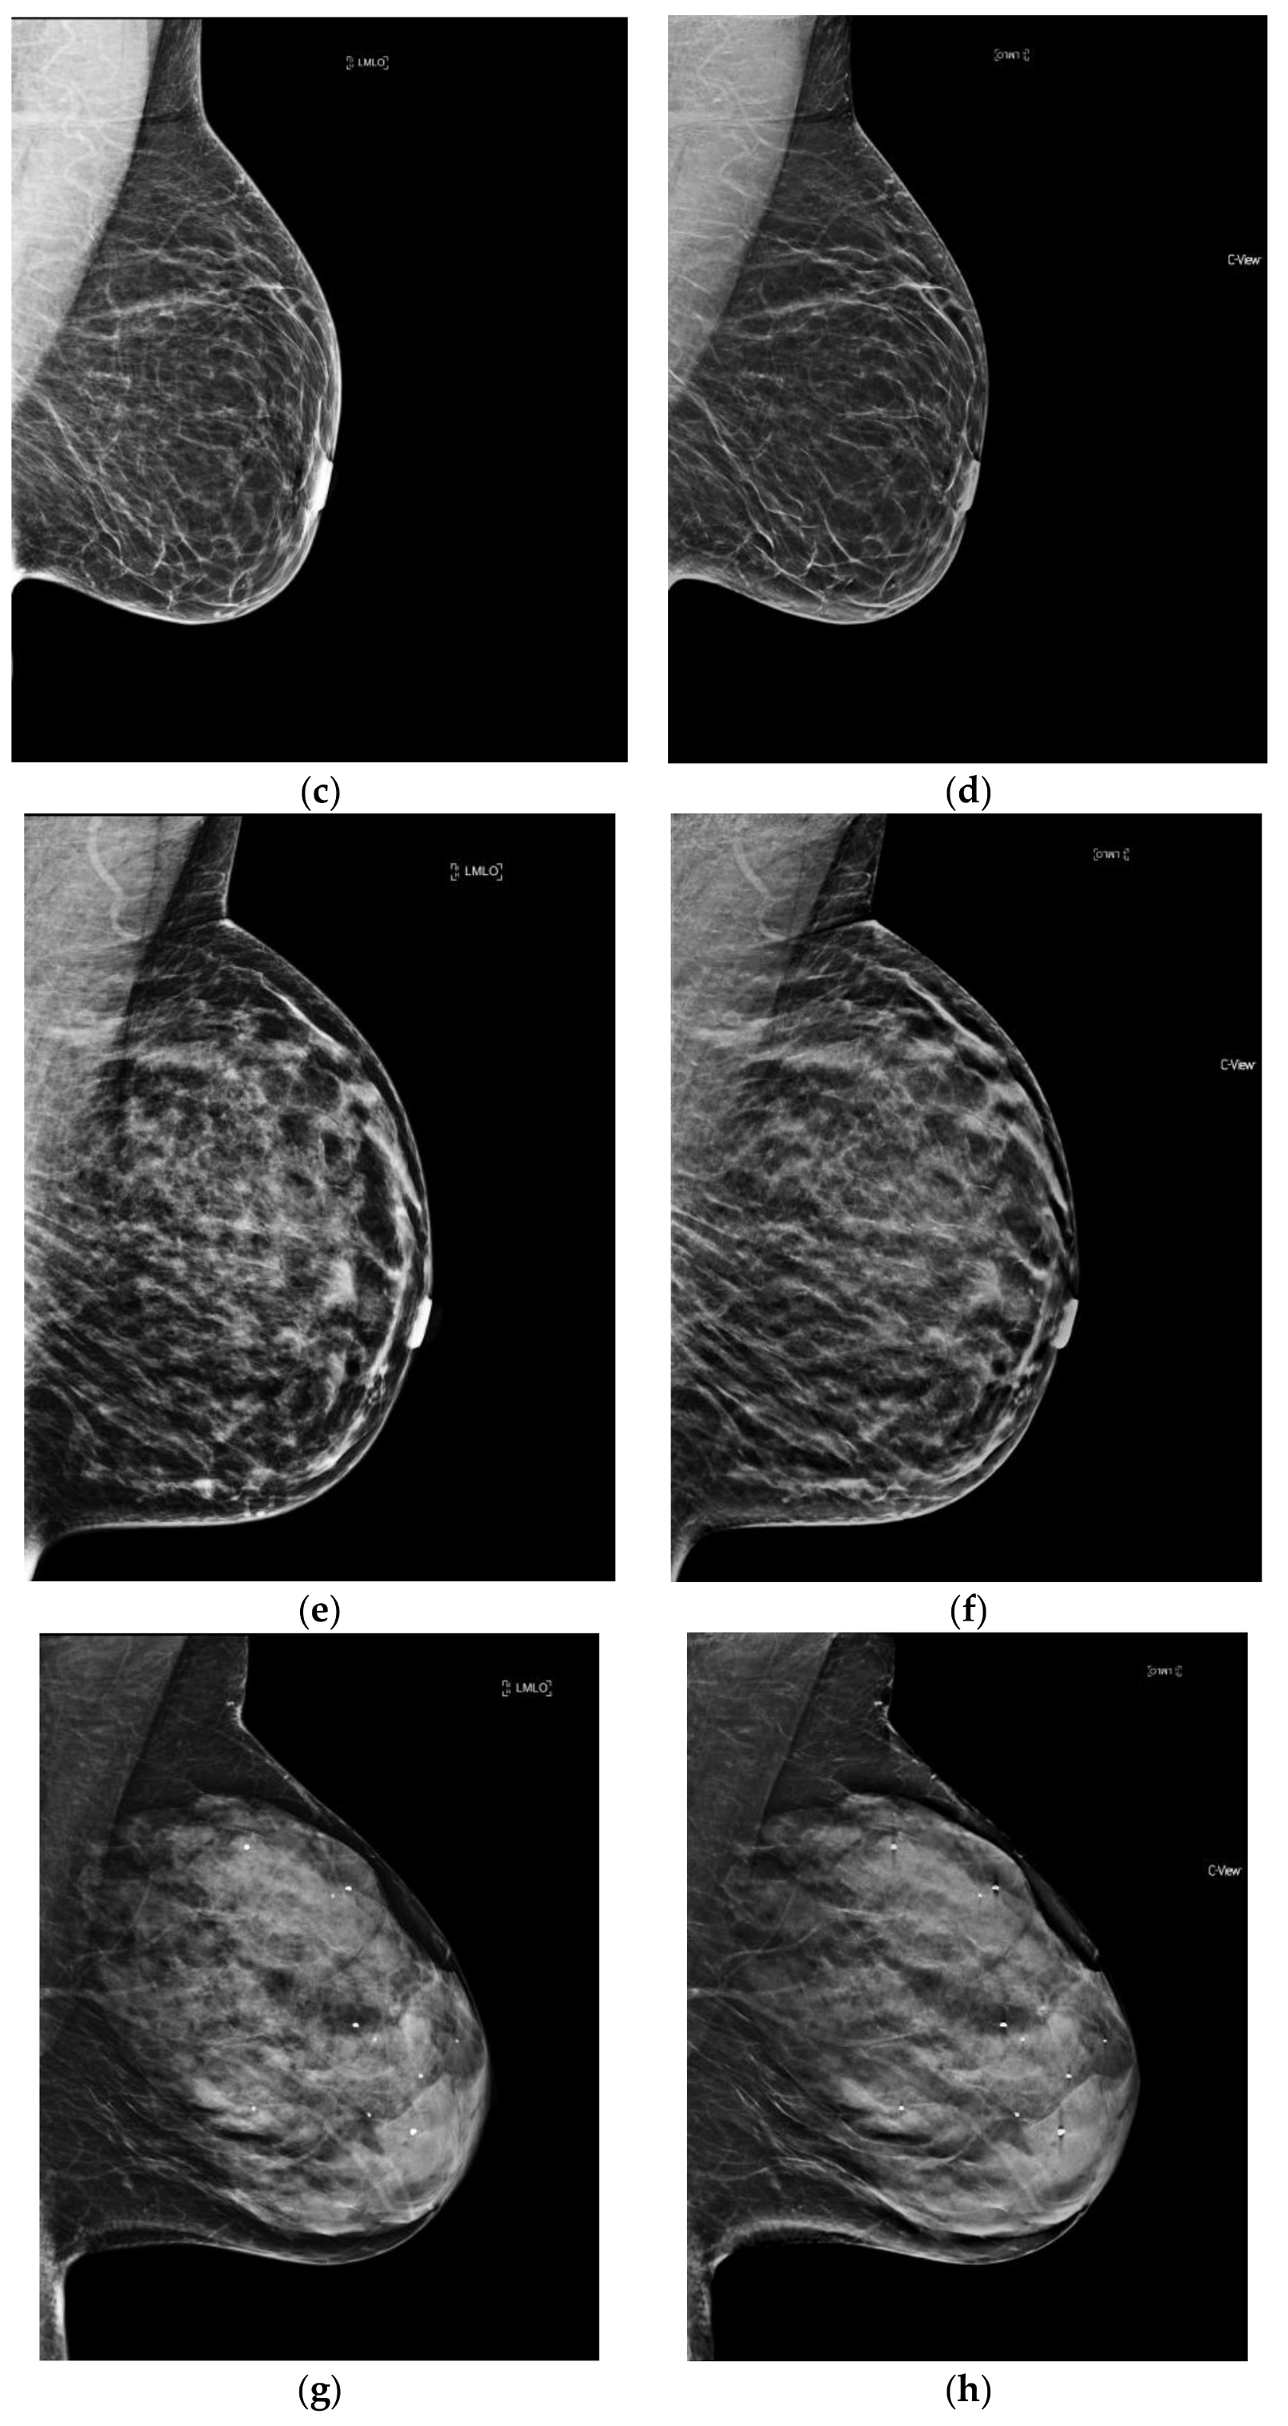

Of note, with synthesized mammography, the recall rate (RR) of women with dense breasts has been shown to approach that of 2D FFDM for women with non-dense breasts (RR dense breasts with s2D+DBT 7.11 vs. RR non-dense breasts with 2D FFDM 7.34%) [31]. Additional studies to subanalyze the effect of breast density on performance outcomes with synthesized mammography are needed. (Figure 1).

Figure 1.

The four categories of breast density on conventional 2D FFDM and synthesized mammography. (a) Predominantly fatty breast 2D FFDM (b) Predominantly fatty breast s2D FFDM (c) Scattered fibroglandular breast 2D FFDM (d) Scattered fibroglandular breast s2D (e) Heterogeneously dense breast 2D FFDM (f) Heterogeneously dense breast s2D (g) Extremely dense breast 2D FFDM (h) Extremely dense breast s2D.